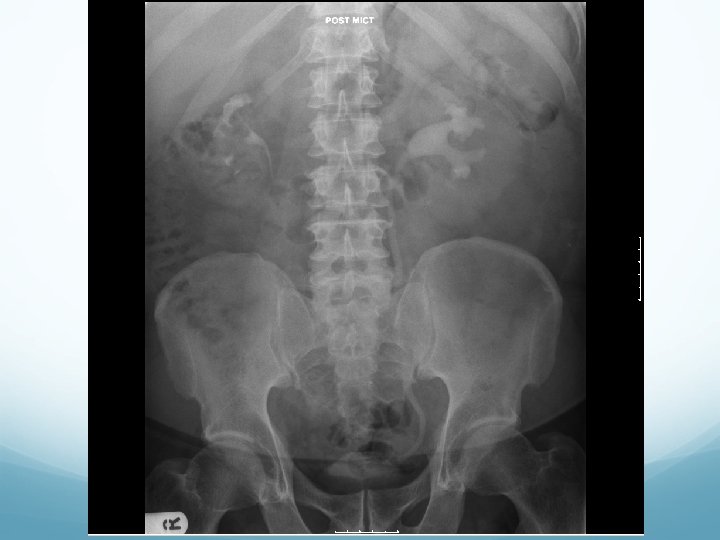

What to look for on a KUB � 90% stones are radio-opaque � Ureteric stones are sausage shaped due to peristalsis of ureters 1. Outline of kidneys 2. Path of ureters � Hila of kidneys L 1 � Tips of transverse processes � SIJ at pelvis 3. Sites of impaction � PUJ � Pelvic Brim � VUJ 4. Rest of abdominal film

1. Outline of kidneys 1. Path of ureters 1. Sites of impaction 1. Rest of abdominal film

What to look for on an IVU � ALWAYS look at KUB first � CT KUB is gold standard, and only option if U+Es are abnormal 1. Nephrogram � � Contrast in kidney Persistent increasingly dense nephrogram in obstruction 2. Pyelogram � Calyces: � � � ? clubbed / more prominent Extravasation of contrast Ureters: � � � Peristalsis: Normal Dilatation Standing column